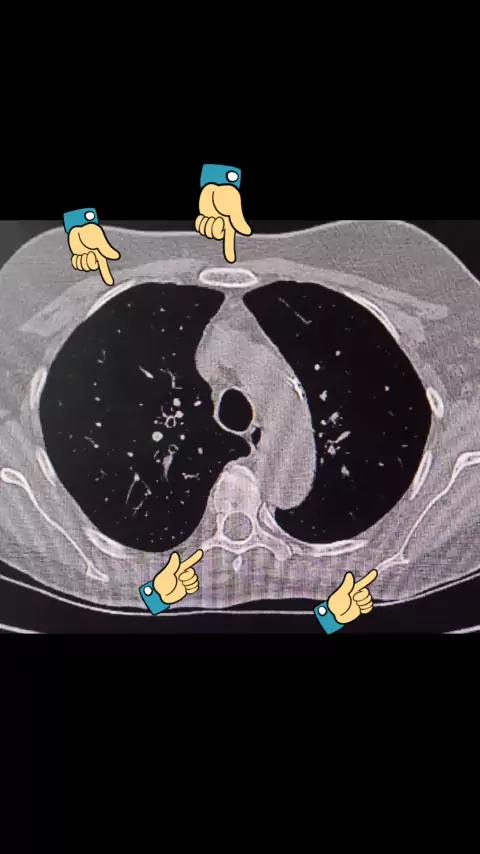

Anatomia seccional Tomografia Tórax- #imagem #tomografia #radiologia #Saúde #corpohumano